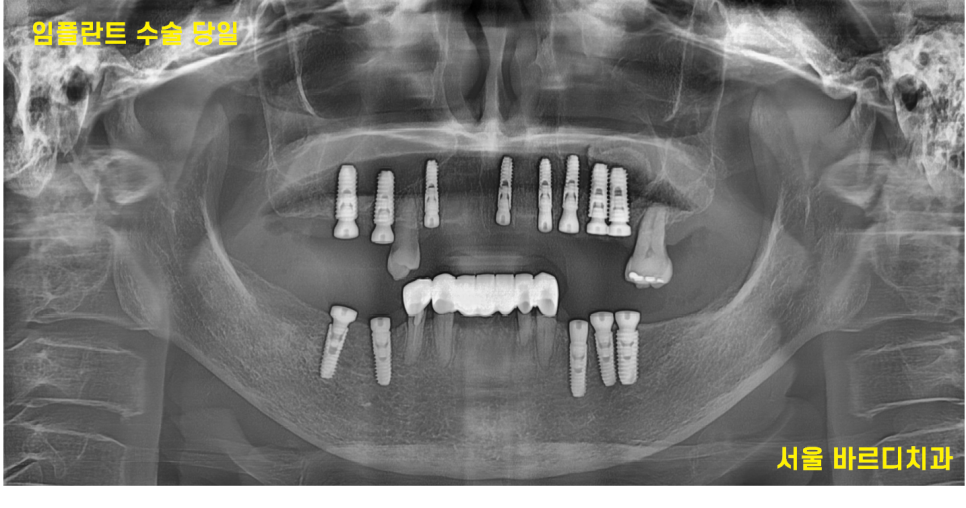

< 수술 당일 >

231018

치료 기간을 단축하기 위해

위아래 13개의 임플란트는 하루에 식립하였습니다.

미리 내비게이션 임플란트 수술 방식으로

예측하였기 때문에

개수가 많아도 하루에 모두 식립이 가능하였습니다.